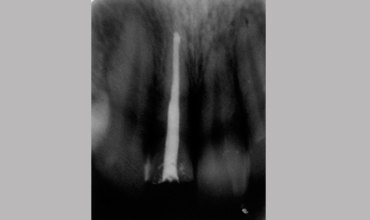

Post Core

Management Of Fractured Tooth With Cast Post & Core